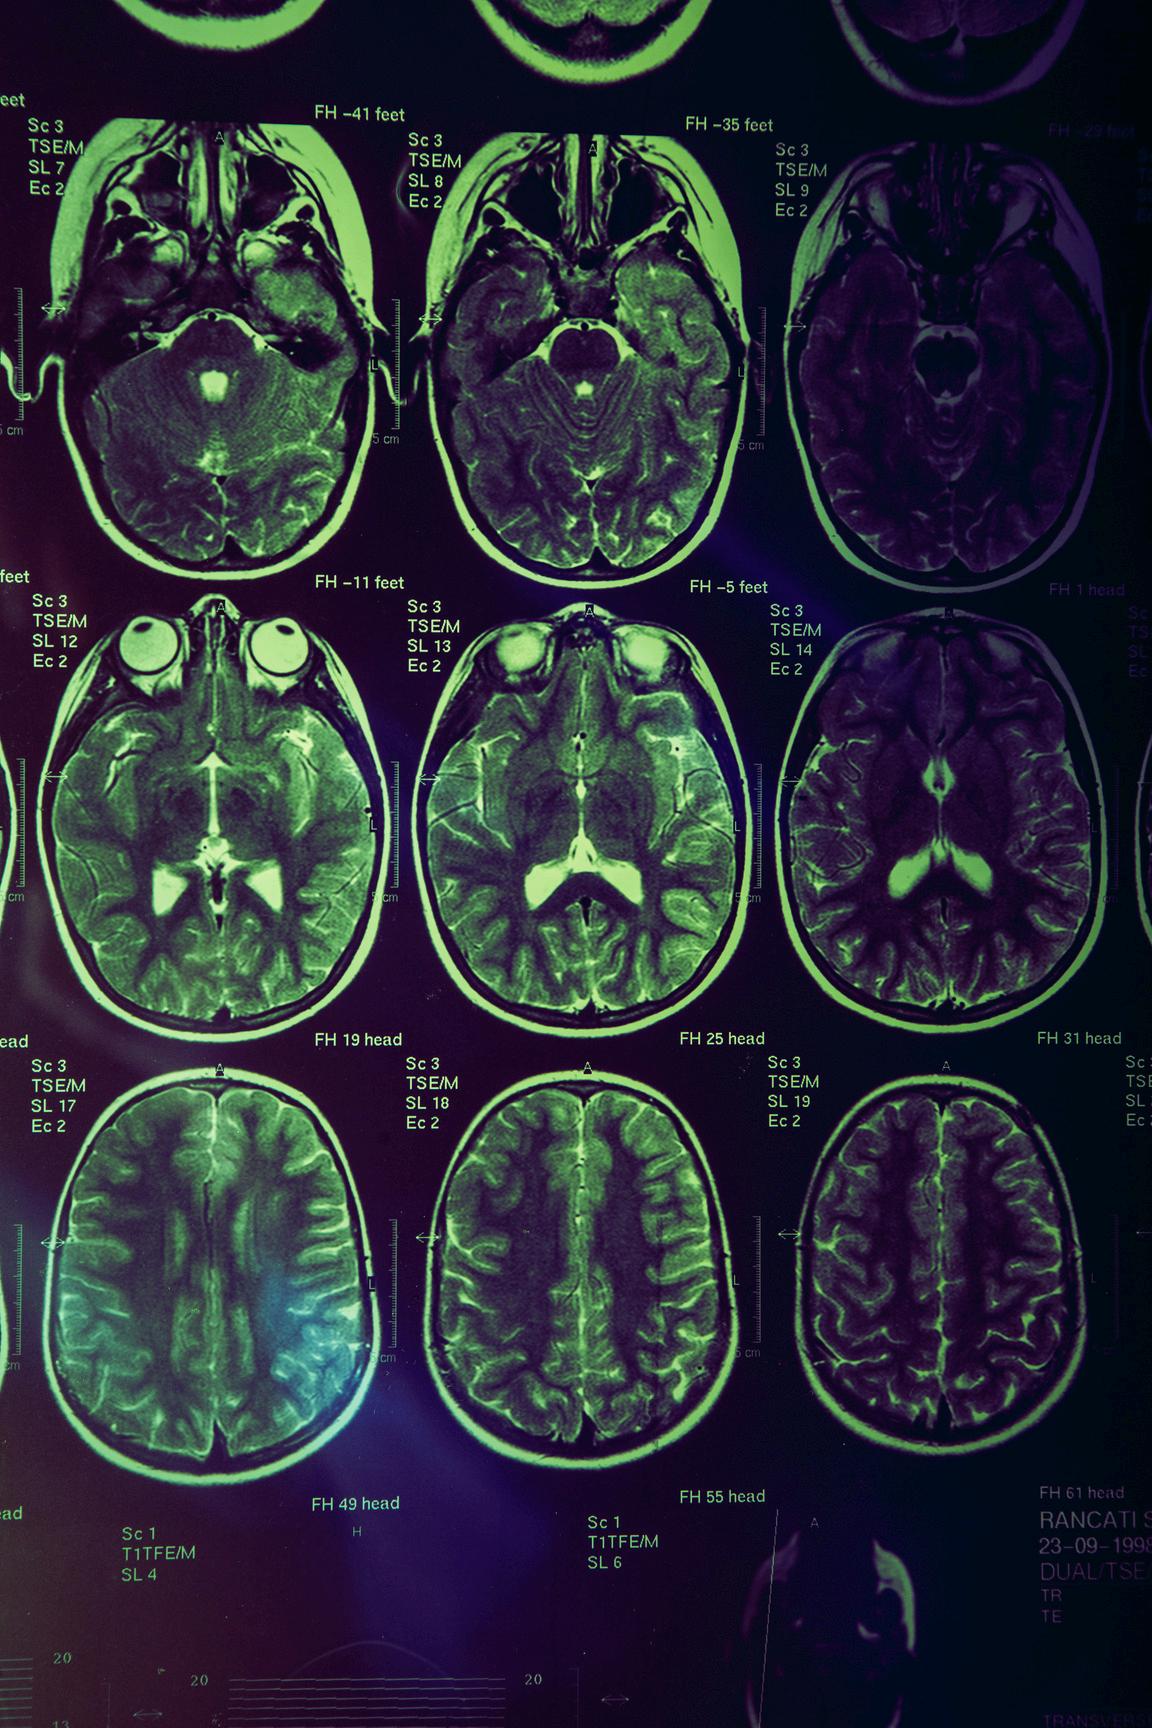

In this unit, students investigate the complex nature of psychological development as well as the role the human brain plays in mental processes and behaviour.

This includes: the interaction between hereditary and environmental factors on a person’s psychological development the process of psychological development (emotional, cognitive and social development) over the lifespan the concepts of normality, neurotypicality and neurodiversity including ADHD and autism spectrum disorder the structure and function of the brain the impact of brain injuries and neurological disorders on an individual’s functioning.